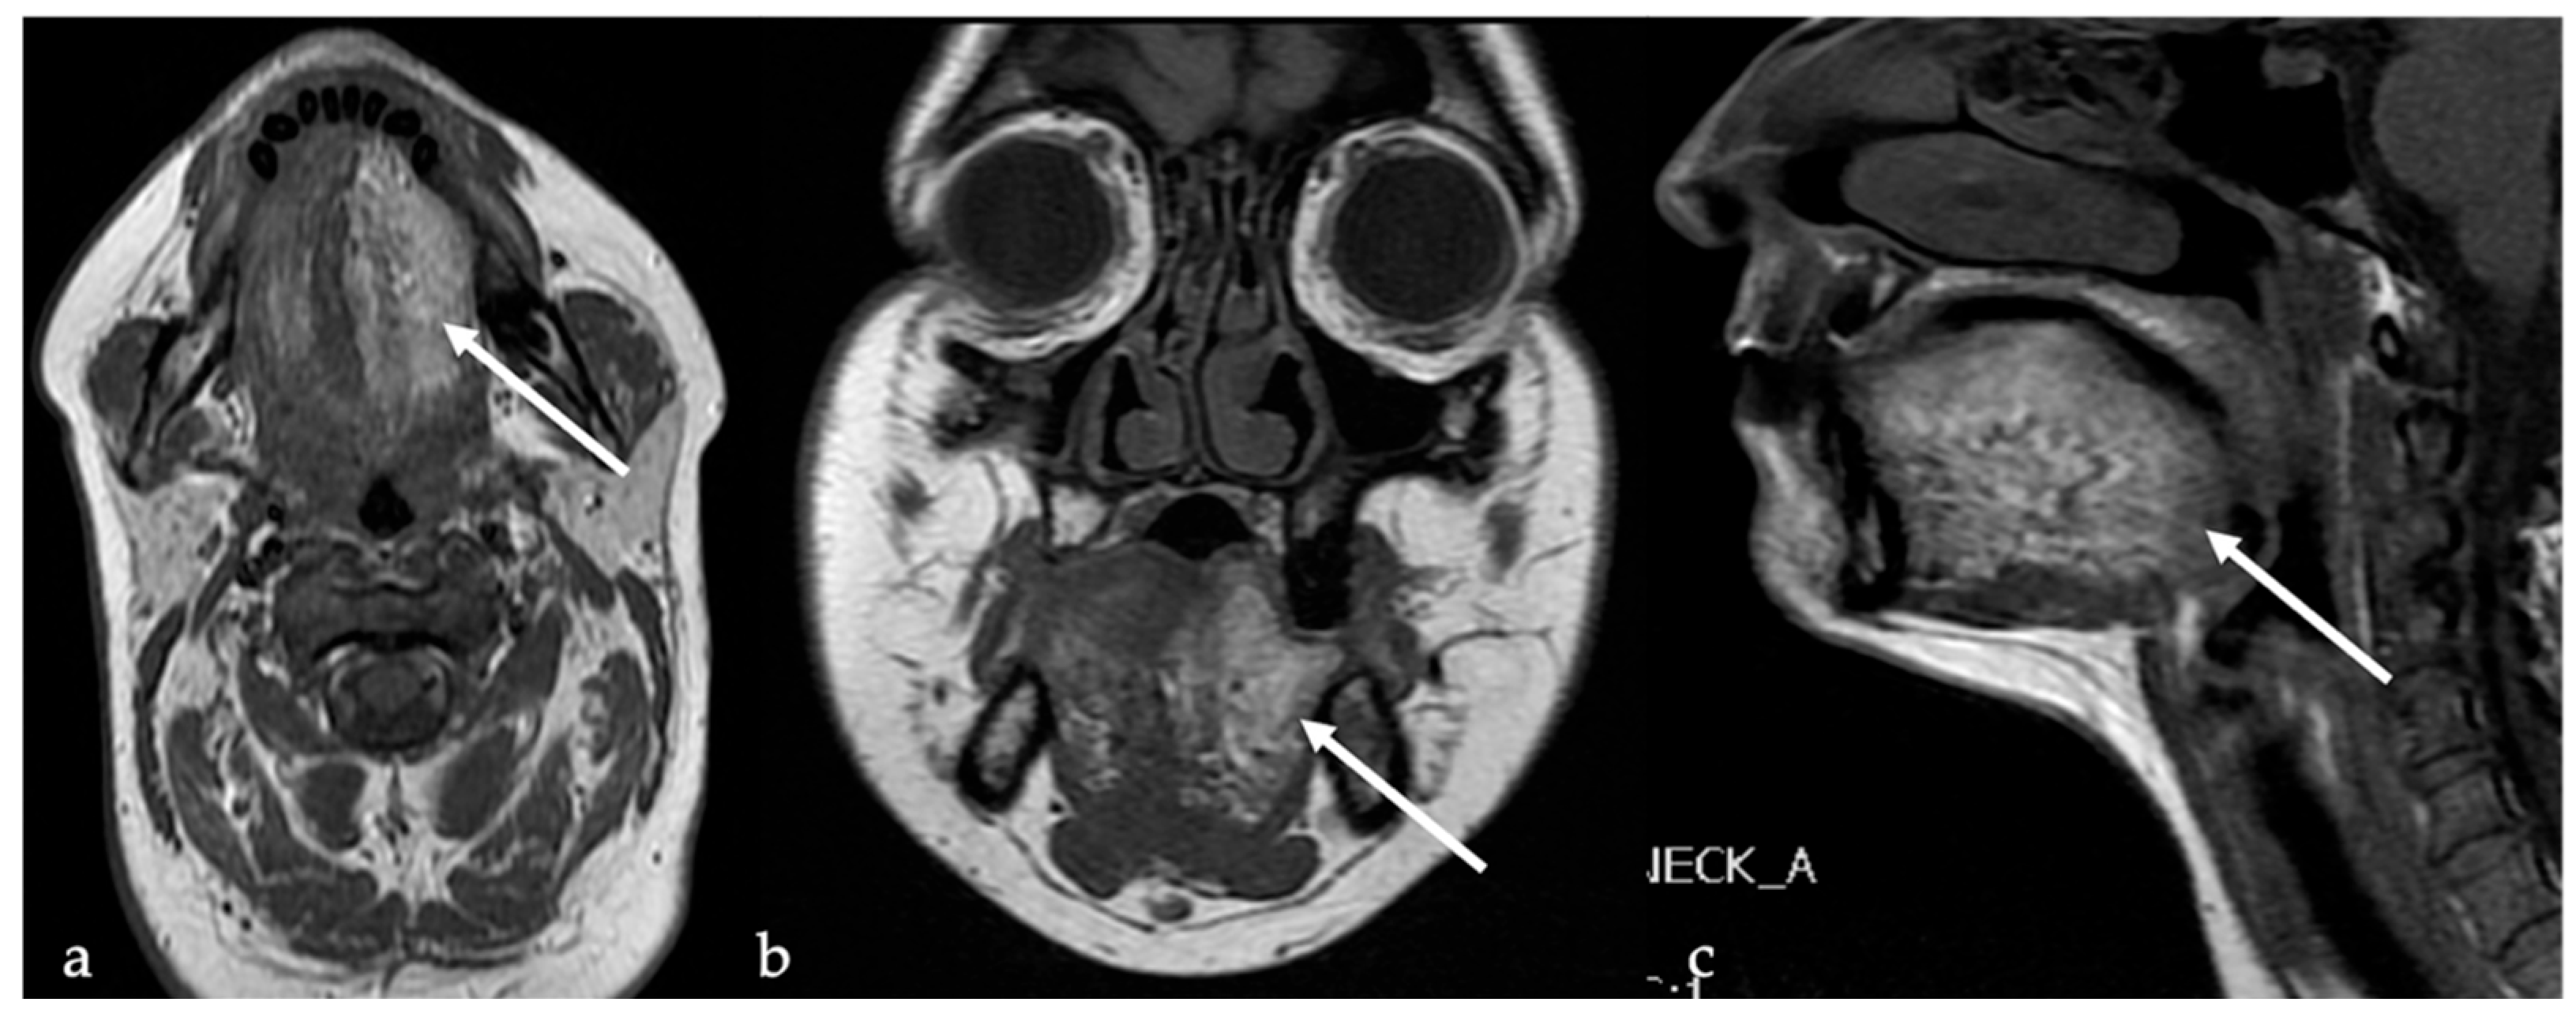

6. Dermoid Cysts

| Dermoid cyst [1,13,14] | CT: free fat and calcified corpuscles (“sack of marbles” sign) | Vascular malformation, epidermoid cysts, lipoma |

| Epidermoid cyst [14] | MRI: high SI on DWI, and restricted diffusion with low values on ADC map | Vascular malformation, dermoid cysts |